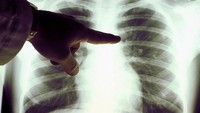

Selanjutnya, ada foto dada seorang pasien COVID-19 (kiri) dan foto dada seseorang dengan paru-paru normal. Foto rontgen ini diambil pada 28 April 2021 lalu di Jerman.